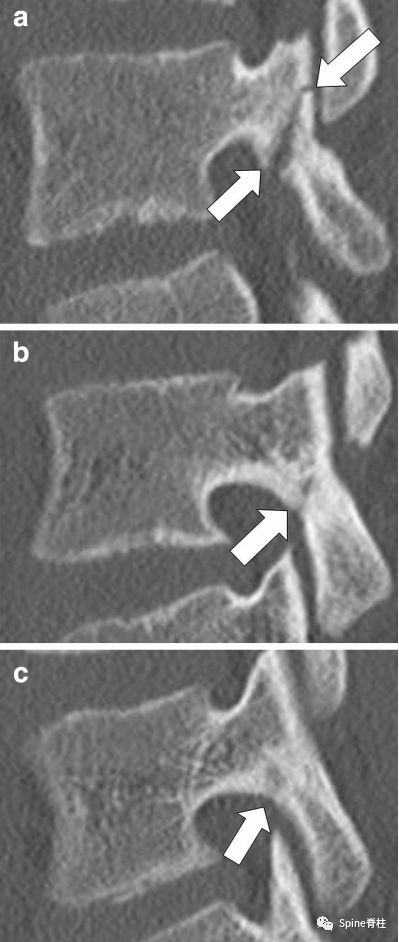

2. 峡部裂的Kaneko分型:

图:Kaneko分型

a为 完全骨折 ,b为 不完全骨折

c为 骨折前期 :峡部皮质骨可见放射缺损区